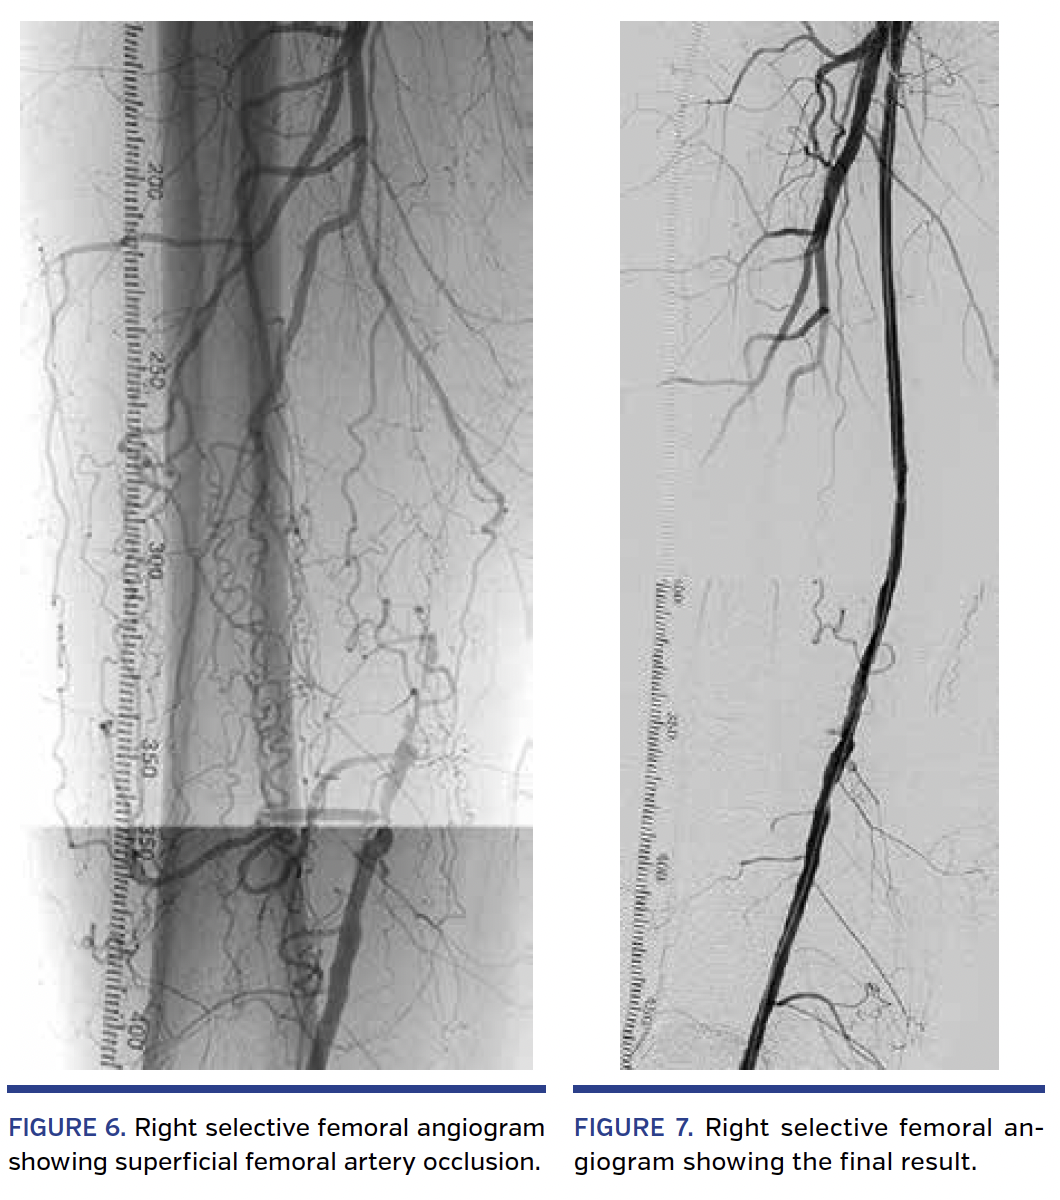

Next, a right leg selective angiogram was performed, confirming a 27 cm-long SFA occlusion (Figure 6). The right femoral access was then inverted, and a short 6 Fr sheath was advanced into the right proximal SFA stump. A tap test was performed confirming a fibrous “hard” CTO. The occlusion was then crossed with the ShockWire backed with a 4 x 100 mm Sterling balloon using the same technique as on the contralateral side. The ShockWire was activated to penetrate the cap of the occlusion and to cross certain segments of the CTO. The ShockWire was successfully advanced across the entire length of the occlusion. After predilation, the CTO was treated with 5 mm drug-coated balloons according to standard technique with an excellent angiographic result and no complications (Figure 7). Postprocedural ankle-brachial indices were 0.97 on the right and 1.05 on the left, significantly improved from baseline.